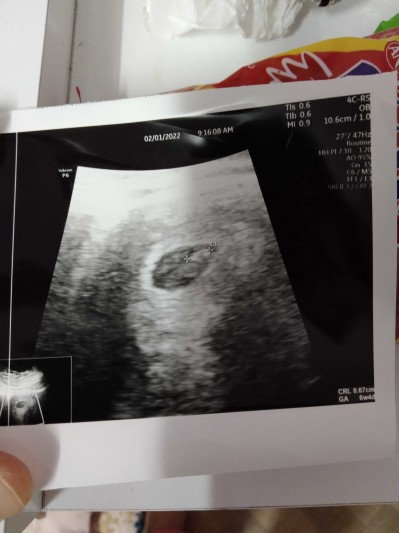

image

6 haftalık Ken geçen hafta duyduk aile hekimi 8 haftalık demişti geç döllenmeymis

Ekledim yoruma canim işaretli yerde canim

Doktorum idrara sıkışık gel su çok iç iyi görürüz o zaman dedi canım aklında olsin seninde inşallah görürsünüz